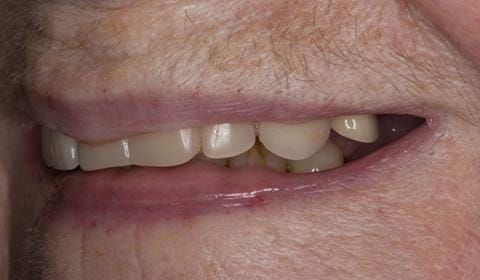

The 'gasket' or 'window' denture - provision of a maxillary cobalt chromium based partial denture

- Poorly fitting cobalt chromium based maxillary partial denture, which has been added to. This exhibited poor retention, stability and tissue fit (support). Unable to wear a new acrylic based denture.

Following consultation and second discussion appointment the patient chose to have option 2 namely, a window denture - maxillary cobalt chromium based partial denture. The clinical situation and treatment process is shown in detail below with photographs. The patient was successfully rehabilitated with this and her quality of life considerably improved. The clinical work was provided by Finlay and the technical work by Rowan.